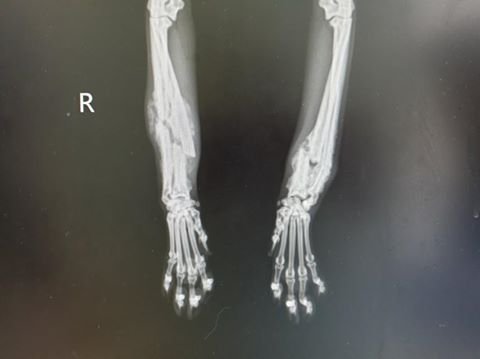

복합골절된 로이의 왼쪽 다리를 수술하는 데만 6시간 반, 부러진 송곳이를 수술하는 데 4시간이 걸렸습니다. 골절 부위에 생긴 가골을 모두 긁어내고 제대로 접합하고 플레이트를 박아 고정해야 했기 때문입니다.

은동이의 왼쪽 다리는 상당 부분 잘못 어긋난 채 붙어버려 다시 뼈를 맞추고 가골 제거하고 난 뒤 일주일 후에 보니 뼈가 기적적으로 잘 붙어 무난하게 2차 수술을 진행했습니다. 부러진 송곳니는 다행히 뼈가 살아있어 발치하지 않고 레진 치료를 하였습니다.